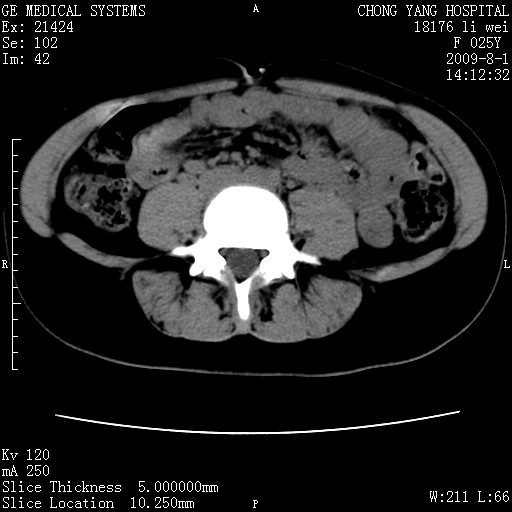

以下是引用pujunzhi在2009-8-1 20:23:00的发言:[br]胸椎旁及背部肌间良性病变,范围广,边界清,沿肌间生长,考虑淋巴管瘤、血管瘤,建议增强扫描。

以下是引用拾荒者在2009-12-30 21:45:00的发言:[br]ct21383:神经纤维瘤病( nf) [br] [br] 神经纤维瘤病。四肢都有,影响美观,四肢上的手术了。[br] [br] [br]谢谢!